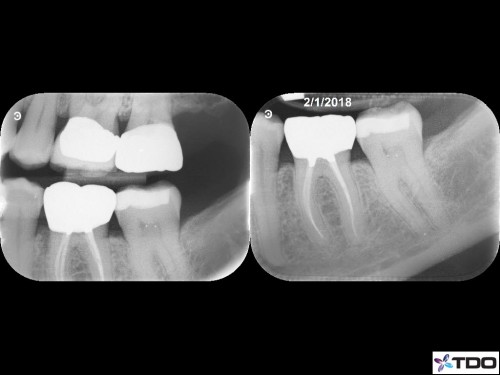

From last week. 59yof. SIP. Hyperemic. 6 canals. 2 visits. Asymptomatic at the second visit. Asymptomatic and functional at the follow-up appointment.